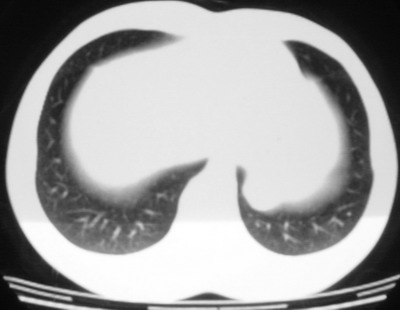

以下是引用余辉在2007-6-16 20:47:00的发言:[br]图像不边续,1左肺下叶膈后囊性病灶,与胃有密切联系,考虑局限性膈膨隆,不排除其他如脓肿等;2左膈肌脚增厚,其前方肝胃间隙内可见球形病灶,左肾上腺病变?进一步检查